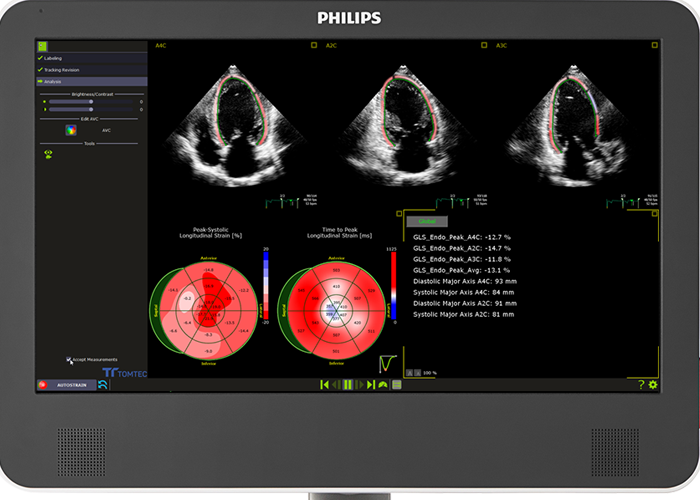

Automated GLS measurement for routine clinical use Now, TOMTEC AutoSTRAIN, powered by advanced automation technology is available on EPIQ CVx. It offers a simple one-button-push strain solution driven by Auto View Recognition and Auto Contour Placement trained on more than 6000 images to ensure the robustness. AutoSTRAIN provides fast and reproducible left ventricle global longitudinal strain (GLS) measurement for everyday clinical use.